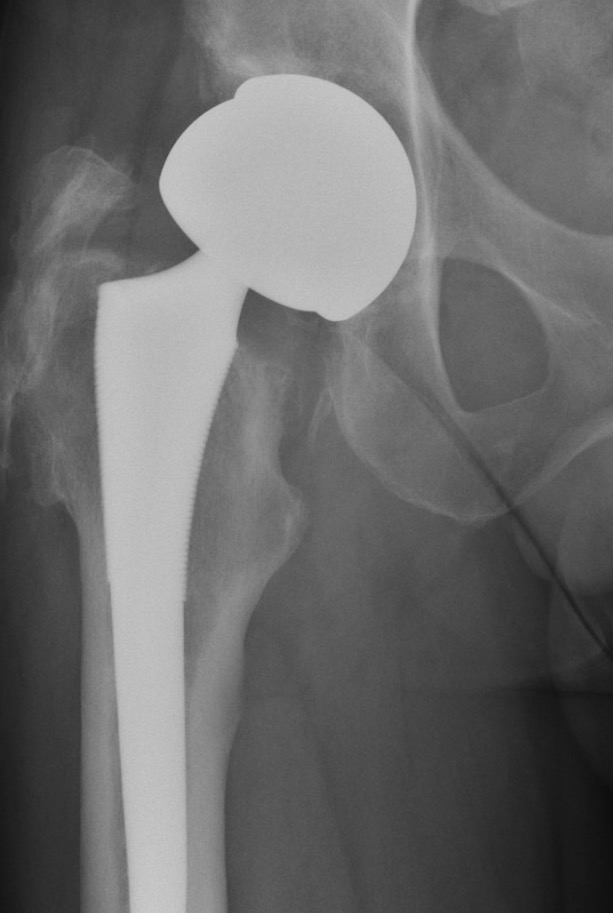

Metal on Metal

Advantage

Large heads

- 30 - 60 mm

- decreases dislocation

- ?improves ROM / function